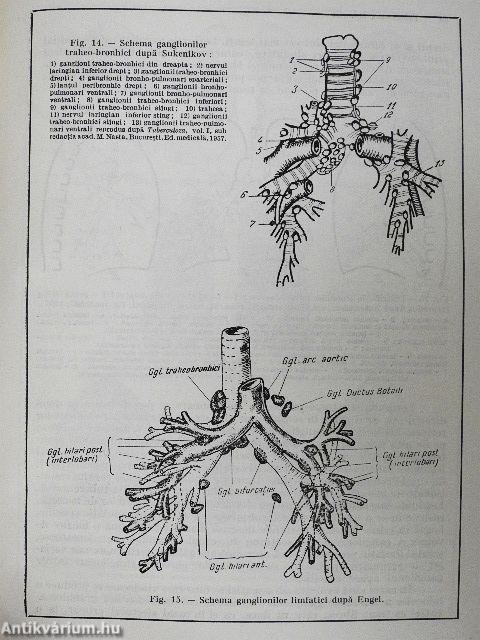

Tuberculoza Infantila

| Megjegyzés: | Fekete-fehér fotókkal, ábrákkal. |